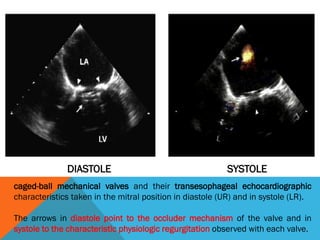

caged-ball mechanical valves and their transesophageal echocardiographic

characteristics taken in the mitral position in diastole (UR) and in systole (LR).

The arrows in diastole point to the occluder mechanism of the valve and in

systole to the characteristic physiologic regurgitation observed with each valve.

DIASTOLE SYSTOLE